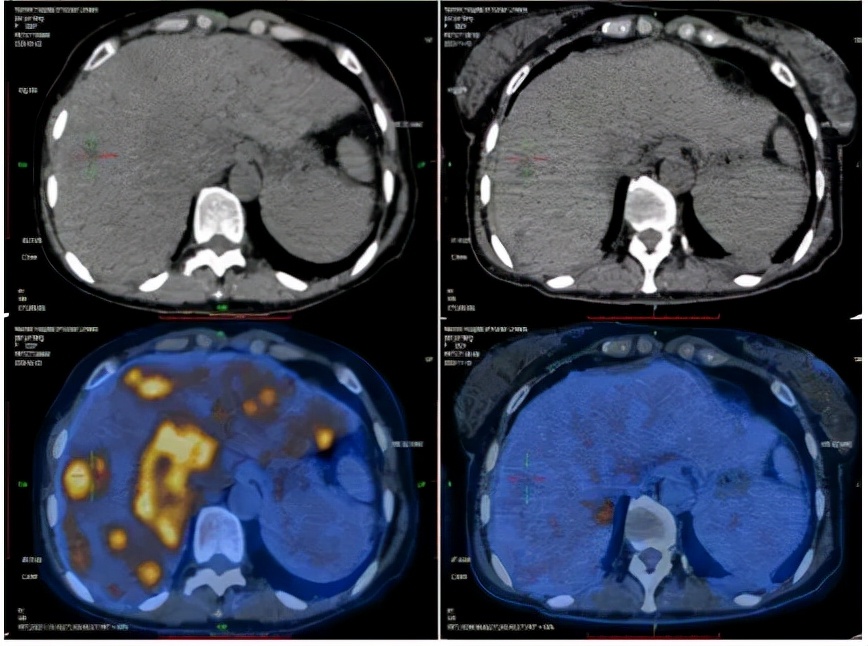

2020-4-22PET-CT提示:1. 胰腺体尾部稍低密度团块;肝内见多发团块、结节灶;肝门区、胰腺周围、腹膜后区多发肿大淋巴结;全身多发骨质密度不均;上述病灶代谢增高,考虑恶性病变,胰腺癌伴全身多发转移;2. 左锁骨上区及胸廓入口处淋巴结,代谢稍增高;不除外转移可能。

2020-11-18PET-CT提示:1.胰腺体部结节,代谢增高;肝实质多发稍低密度团块、结节灶,代谢增高;全身多发骨质密度不均,代谢稍增高;上述考虑胰腺癌伴多发转移灶治疗后改变,少许活性尚存。2.左锁骨上区及胸廊入口处淋巴结,较前缩小,代谢减低;肝门区、胰腺周围及腹膜后区高代谢淋巴结未见明显显示;上述考虑转移灶经治疗后改变,活性受抑

2020-4-22 2020-11-18